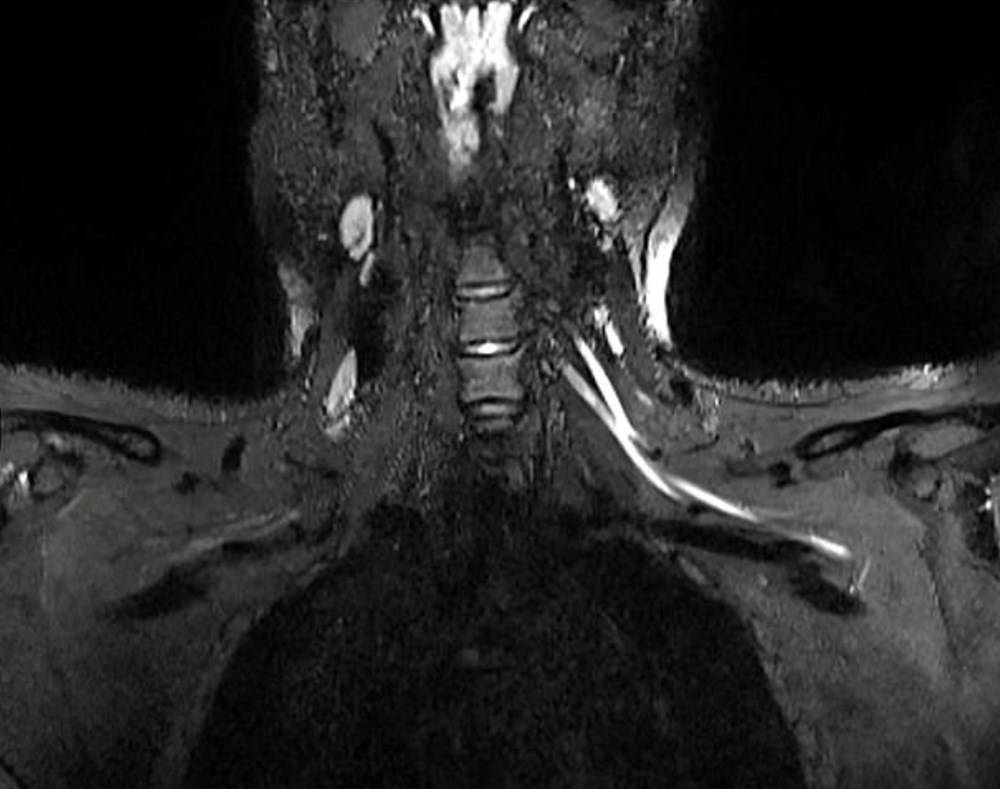

Radiology dergisinde yayımlanan çalışmanın başyazarı Doktor Swati Deshmukh, konuya ilişkin yaptığı açıklamada, “Ağrı boynunuzdaki, dirseğinizdeki veya bileğinizdeki sorunlardan kaynaklanıyor olabilir ve bunu anlamanın en iyi yolu MRI veya ultrasondur. Yaptığımız çalışmayla çok küçük sinirleri bile gösteren gelişmiş görüntüleme sunuyoruz. Bu da sorunun nerede olduğunu tespit etmemize, ciddiyetini değerlendirmemize ve buna neyin neden olabileceğini önermemize yardımcı oluyor” ifadelerini kullandı.

Bununla birlikte Doktor Deshmukh, koronavirüsün aşırı bağışıklık tepkisini tetiklemesinden dolayı, vücut tarafından üretilen antikorların sadece enfekte hücrelere değil, sağlıklı dokulara da saldırmaya zorlayarak ciddi semptomlara neden olduğunu söyledi. Bilim insanı, olayın ardından sinir sisteminde de şiddetli iltihaplanma görülebileceğini açıkladı.

Doktor Deshmukh, “Ciddi Covid-19 vakalarında vücudun bağışıklık tepkisinin akciğerlere saldırmasına benzer bir şekilde, bazı hastaların bağışıklık tepkisi sinir sistemini etkileyebilir” dedi.